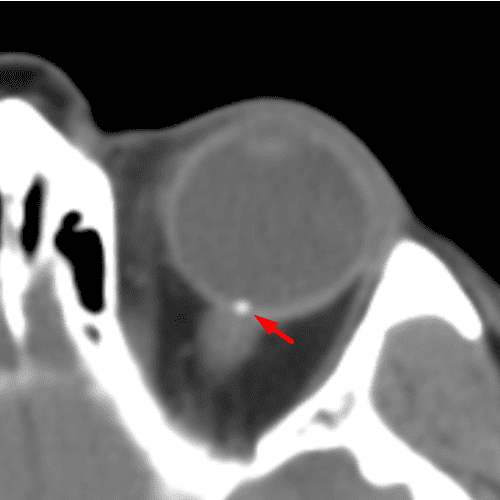

Calcific Scleral Plaques

Case 21